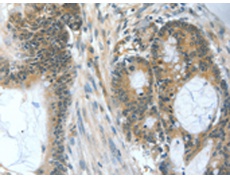

IHC positive control: |

Human colon cancer and Human esophagus cancer |